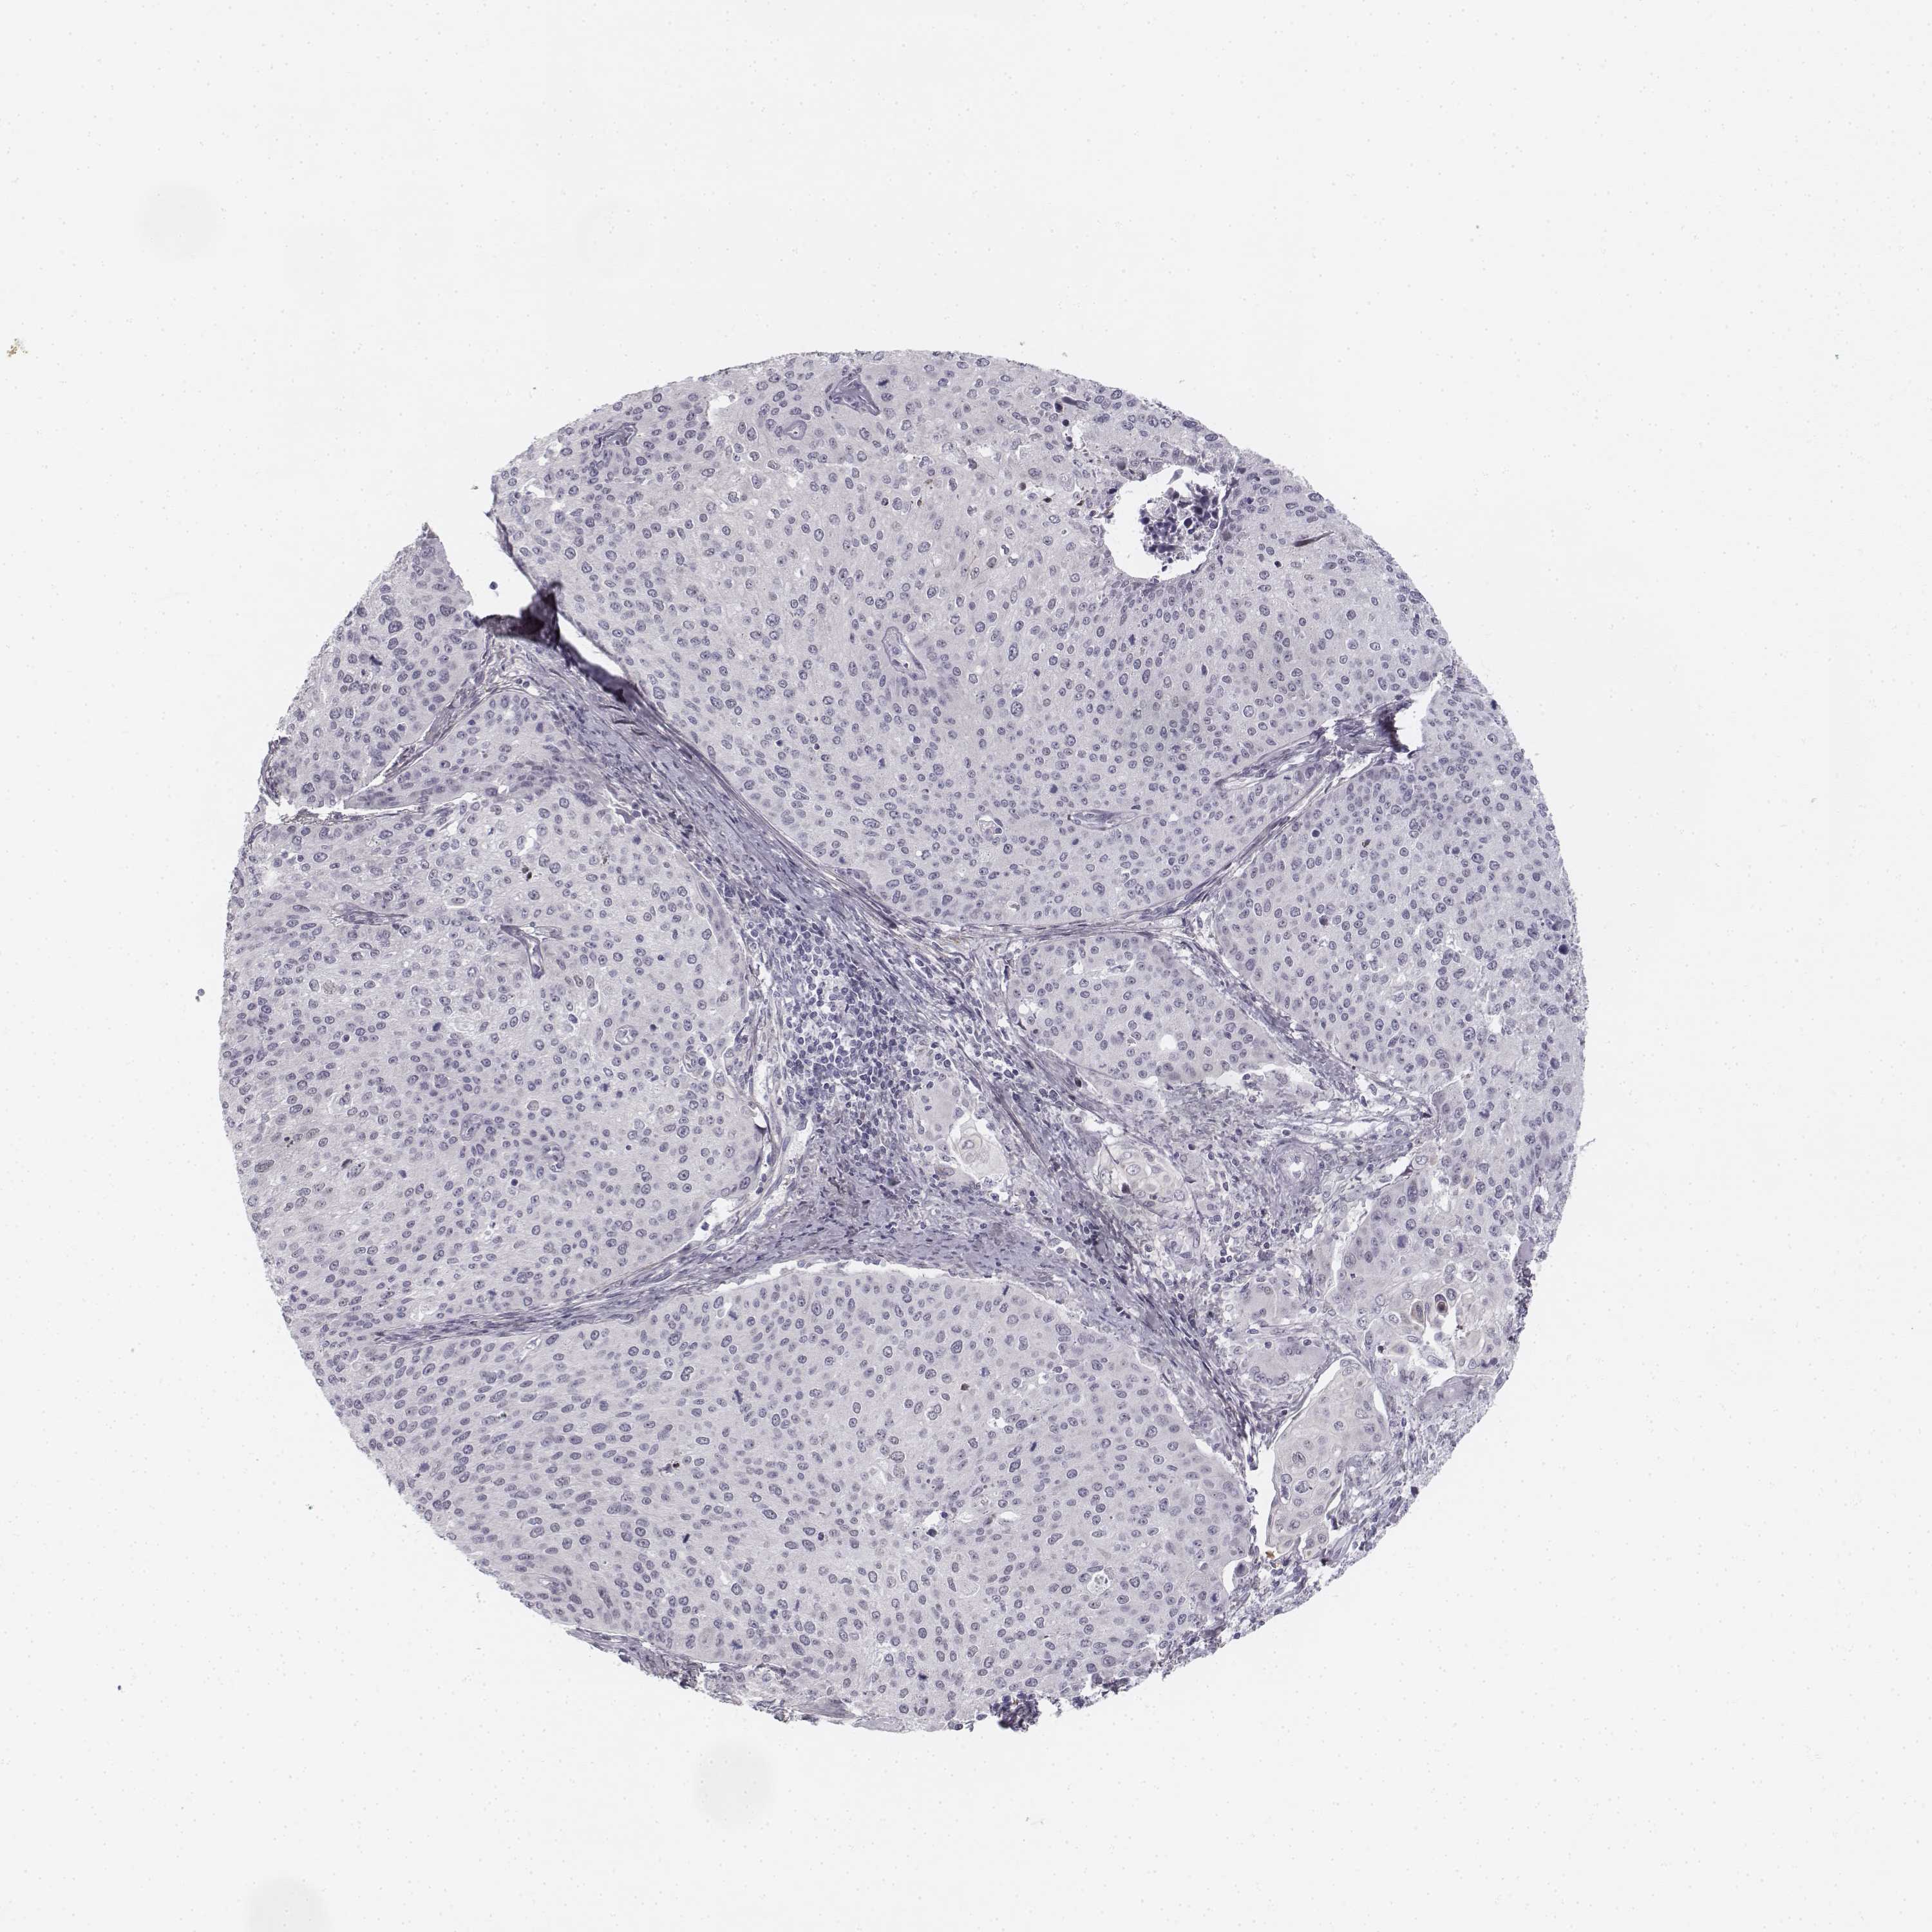

CERVICAL CANCER - Protein expressioni

A mouse-over function shows sample information and annotation data. Click on an image to view it in a full screen mode. Samples can be filtered based on level of antibody staining by selecting one or several of the following categories: high, medium, low and not detected. The assay and annotation is described here.

Note that samples used for immunohistochemistry by the Human Protein Atlas do not correspond to samples in the TCGA dataset.

Antibody stainingi

Antibody staining in the annotated cell types in the current human tissue is reported as not detected, low, medium, or high, based on conventional immunohistochemistry profiling in selected tissues. This score is based on the combination of the staining intensity and fraction of stained cells.

Each image is clickable and will lead to virtual microscopy that enables deeper exploration of all samples and also displays staining intensity scores, fraction scores and subcellular localization as well as patient and tissue information for each sample.

Antibody HPA039714

Staining

High

Medium

Low

Not detected

Intensity

Strong

Moderate

Weak

Negative

Quantity

>75%

75%-25%

<25%

None

Location

Nuclear

Cytoplasmic/membranous

Cytoplasmic/membranous,nuclear

Squamous cell carcinoma, NOS

Adenocarcinoma, NOS